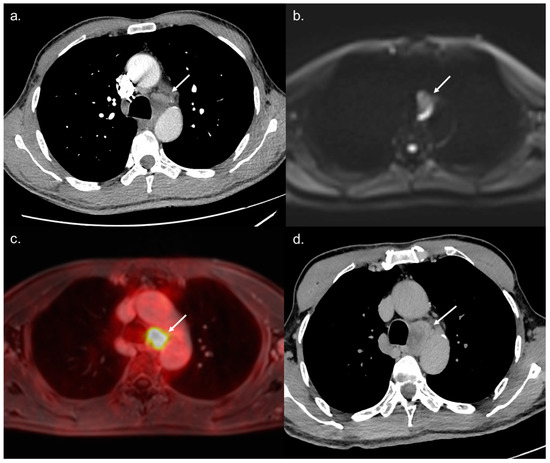

All 14 metastatic sites were correctly identified on the WB-PET/MRI, although only 7 of 16 individual pulmonary metastases (44%) were seen (Figure 2). On the CT-CAP/liver MRI dataset, six metastatic sites were correctly identified (6/14; 43%), resulting in a significantly lower sensitivity (43% vs. 100%, p = 0.002). Notably, all 10 individual bone metastases were missed on the CT-CAP/liver MRI (Figure 3), as well as two mediastinal lymph nodes (Figure 4) and one retroperitoneal lymph node involvement (Figure 3).

The WB-PET/MRI lead to changes in therapeutic management in 10 of 104 patients (9.6%). Metastatic lesions were identified by the WB-PET/MRI in two BCLC stage C patients referred before liver transplantation (Figure 3) and in five BCLC stage C patients referred before TARE (Figure 2 and Figure 4).

Figure 4. A 68-year-old BCLC C patient referred to WB-PET/MRI before TARE. The CT-CAP performed (a) showed a 12 × 25 mm large mediastinal lymph node of indeterminate nature. The WB-PET/MRI revealed hyperintensity on b800 s/mm2 DWI (b) with hypermetabolism on 18F-FDG-PET (c) suggestive of metastatic involvement. Followup performed two months later confirmed the metastatic nature of the lymph nodes with rapid increase in size and necrosis (d).